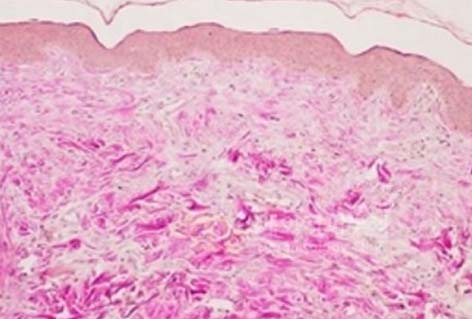

콜라겐 섬유의 밀도와 구조가 개선된 것을 확인할 수 있습니다.

시술전

시술 30일 후